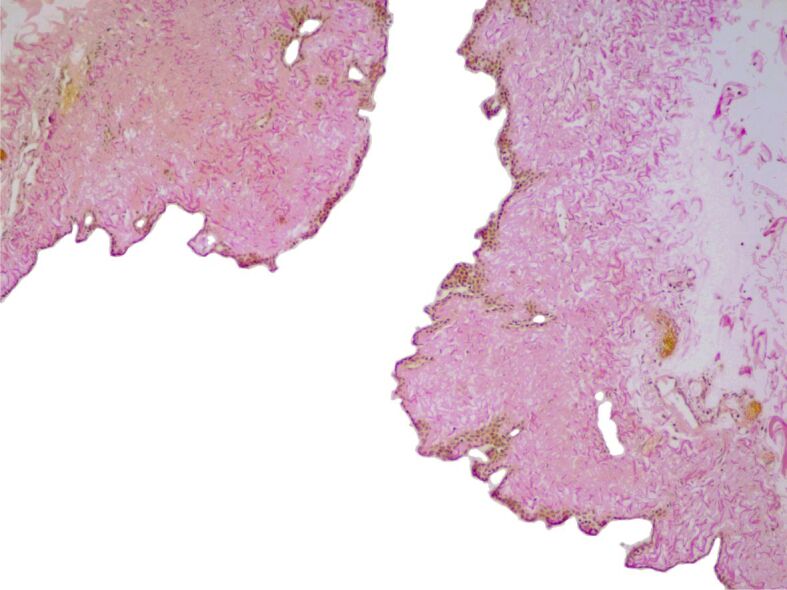

心包囊肿(PCs)或胸膜心包囊肿是一种罕见的先天性纵隔病变,发病率约为十万分之一。它们通常没有症状,是在常规胸部成像检查或尸检时偶然发现的。本研究对在罗马尼亚雅西肺病诊所接受治疗的 6 年系列 PCs 的临床病理结果进行了回顾性评估。共评估了五例肺结核患者,其中四例为女性,一例为男性。所有患者均表现出不同的症状,如呼吸困难、胸痛、慢性咳嗽、疲劳、心悸和上腹痛。四例患者的囊性病变位于左右心膈角,一例患者的囊性病变位于中央纵隔。病灶中含有液体,最大直径在 35 至 95 毫米之间。手术切除组织的显微镜检查显示,结缔组织壁很薄,没有任何相关的平滑肌细胞。疏松的结缔组织带内衬一层无细胞不典型性的间皮细胞,其中一例显示出离散的乳头状突起。虽然 PCs 是罕见的偶然发现,但在纵隔囊肿的鉴别诊断中应考虑到它们,尤其是当它们与非特异性症状相关时。此外,考虑到PC可能会引发严重的并发症,因此应彻底检查PC,以便对患者进行适当的治疗。

Pericardial cysts (PCs) or pleuropericardial cysts are rare congenital mediastinal lesions with an approximate incidence of one in 100 000 persons. Usually, they are asymptomatic, being incidentally discovered during a routine chest imaging examination or an autopsy exam. The study involved a retrospective evaluation of clinicopathological findings in a 6-year series of PCs, treated in the Clinic of Pulmonary Diseases, Iaşi, Romania. A group of five cases of PCs, four females and one male, were evaluated. All patients displayed different symptoms, such as dyspnea, chest pain, chronic cough, fatigue, palpitation, and epigastric pain. The cystic lesions were located in the right and left cardiophrenic angle, in four cases, and in the central mediastinum in a single case. The lesions had a fluid content and a maximum diameter that ranged between 35 and 95 mm. The microscopic examination of the surgical resection tissues revealed a thin connective tissue wall without any associated smooth muscle cells. The loose connective tissue band was lined by a layer of mesothelial cells with no cellular atypia, which displayed discrete papillary projections, in one case. Although PCs are rare incidental findings, they should be considered in differential diagnoses of mediastinal cysts, especially as they are associated with non-specific symptoms. Furthermore, considering the possibility of development of severe complications, PCs should be thoroughly explored for suitable patients' management.